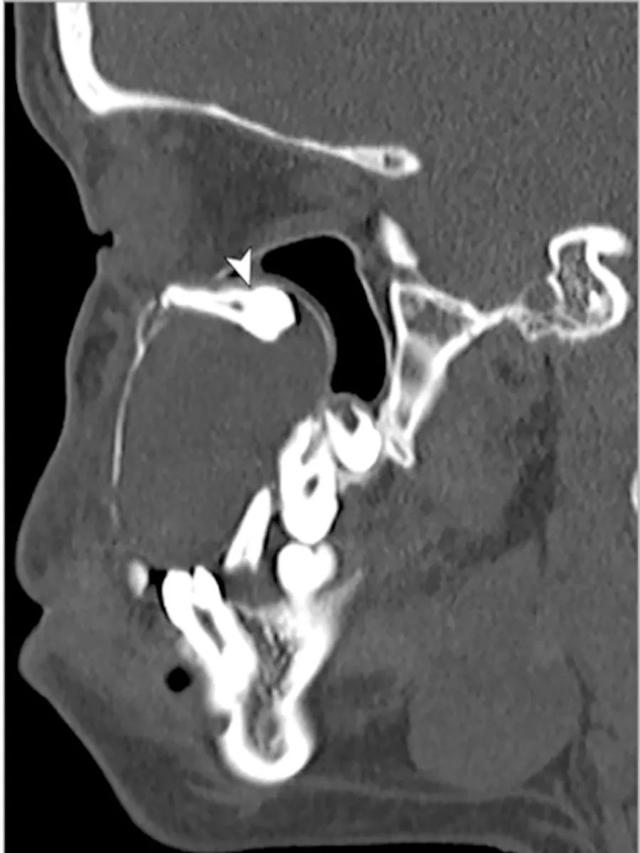

头CT显示,肿物右前上颌骨与上颌窦和眶底毗邻,呈相对球形(直径4cm),并在肿物上缘可见一颗阻生前磨牙(图)。